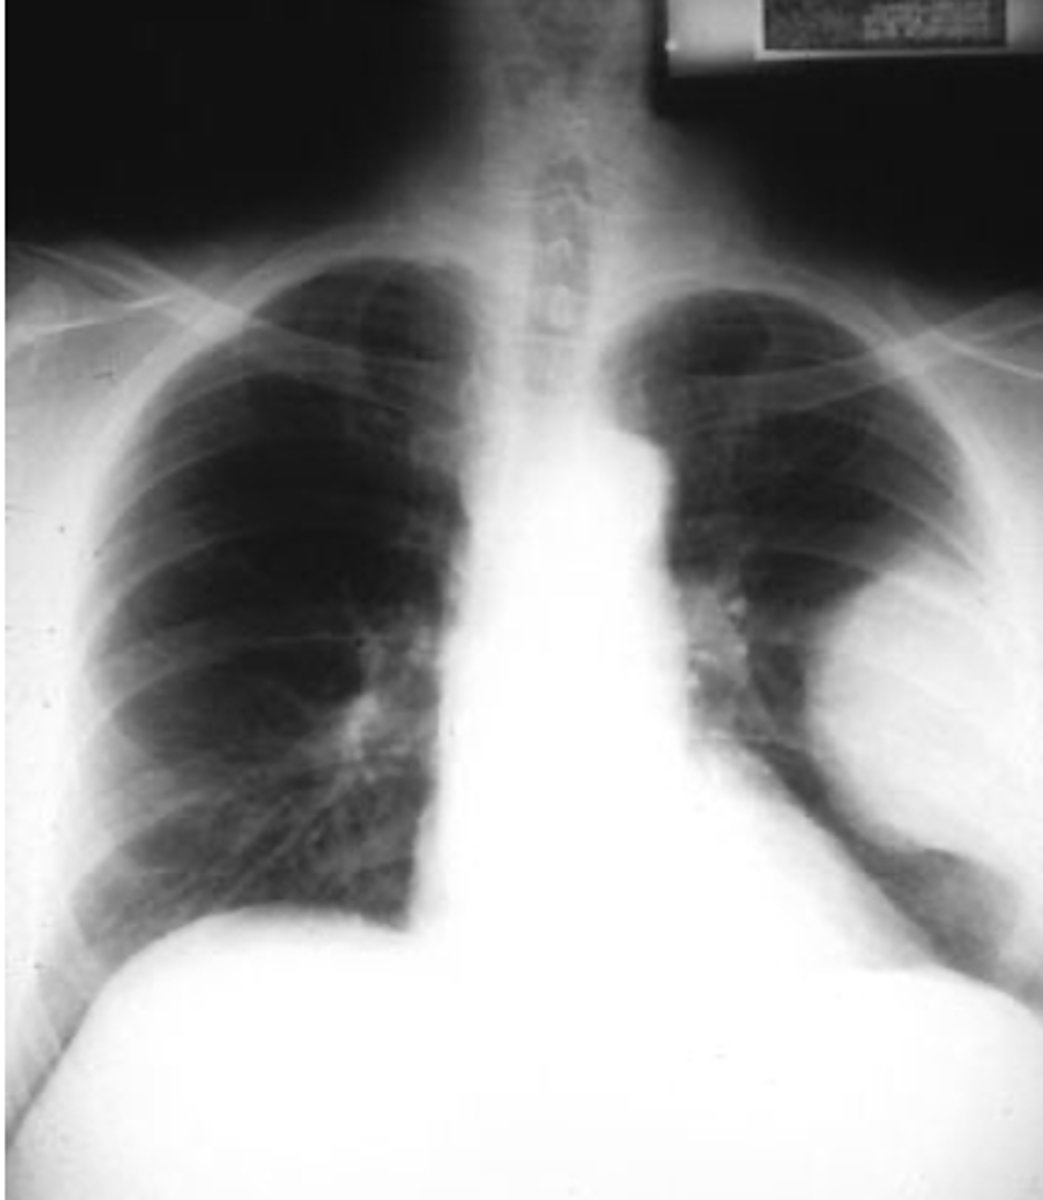

bronchiectasis

Dx

<p>Dx</p>